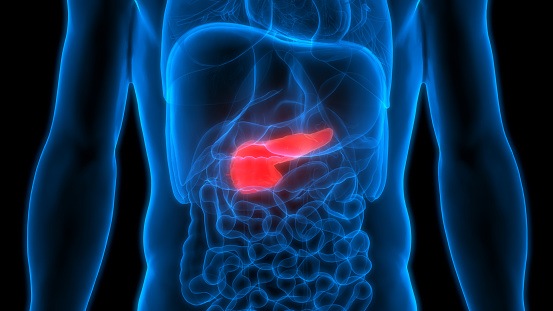

A large study spanning 195 countries found that colorectal and pancreatic cancer rates have increased by 10% between ...Kerri FitzgeraldColorectal Cancer | March 19, 2025

The addition of cisplatin to Abraxane® (nab-paclitaxel) and Gemzar® (gemcitabine) improved survival in patients with ...Kerri FitzgeraldColorectal Cancer | October 8, 2019

Circulating tumor DNA detected through liquid biopsy is an independent predictor of patients with colorectal cancer ...Kerri FitzgeraldPancreatic Cancer | March 19, 2025

A study published in Nature found that the movement of certain fungi from the gut to the pancreas can increase the risk ...Kerri FitzgeraldEsophageal Cancer | March 19, 2025

Patients with type 2 diabetes who are treated with dipeptidyl peptidase-4 (DPP-4) inhibitors are at risk for developing ...Kerri FitzgeraldColorectal Cancer | August 28, 2019